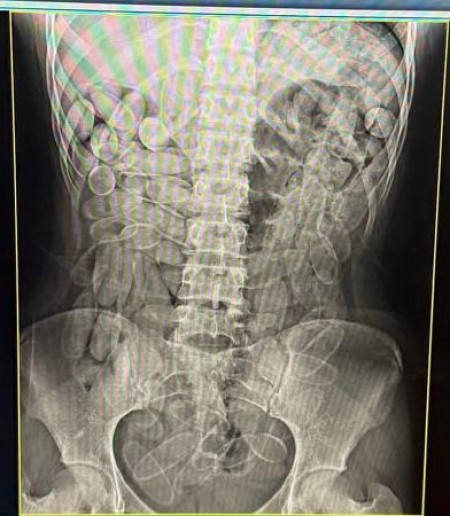

Mulheres confessaram que cada uma engoliu 102 cápsulas de pasta base

As duas foram encaminhadas ao Pronto-Socorro de Corumbá, onde exames de raio-x confirmaram a presença de cápsulas no organismo. Em seguida, elas confessaram ter ingerido 102 unidades cada uma.Ao todo, a apreensão resultou em aproximadamente 2,2 quilos de droga.